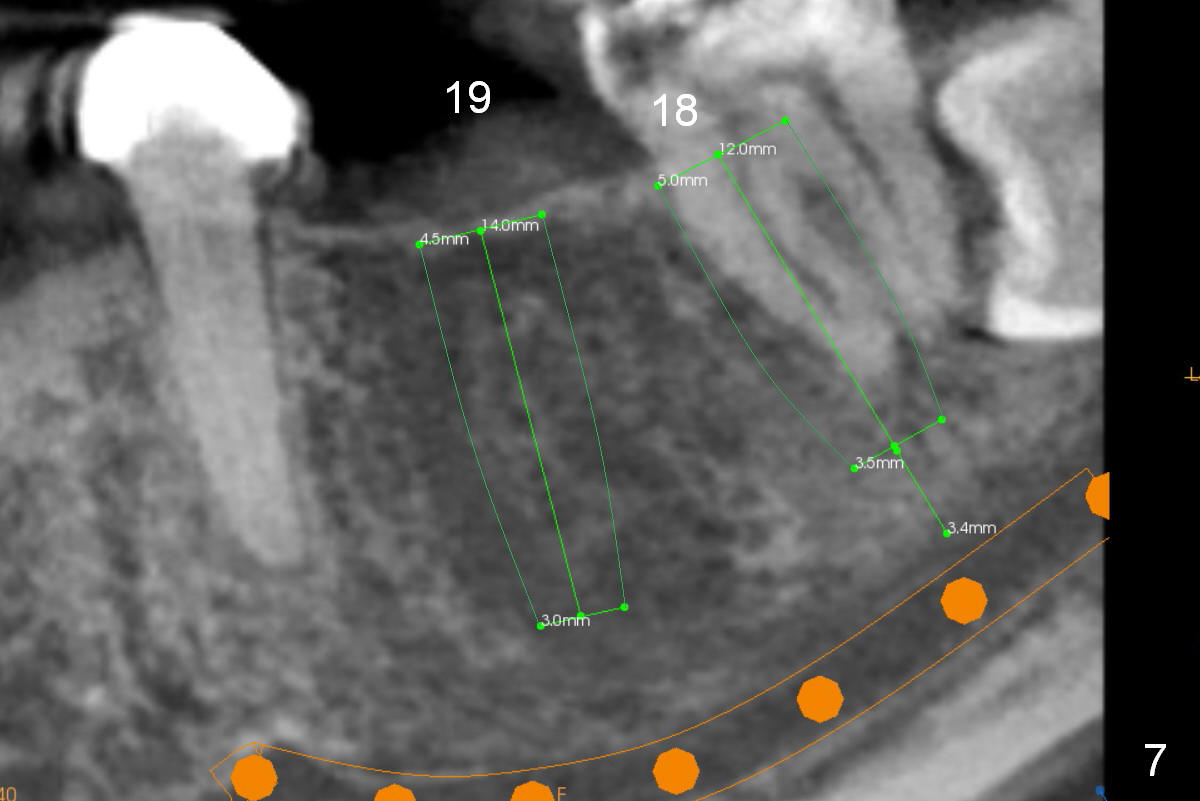

A 35-year-old lady (YL) has periodic nocturnal pain of the lower left quadrant. There is open buccal margin at the abutment of #18 (Fig.1 (from panoramus)). When the pontic and the retainer are removed (Fig.2), there is a large buccal subgingival carious lesion at the tooth #18. The latter has 2 roots, although close to each other. If the extraction turns out to be difficult, section the tooth (Fig.3 red line (no antibiotic)). To avoid contacting the tooth #17, place an implant at the mesial socket of #18 (Fig.5,7). Although it appears that the tooth #20 has no periapical radiolucency (Fig.6,7), the crown will be removed for diagnosis. A 3-unit provisional will be fabricated after an implant is placed at #19 (Fig.7,8) in the same appointment.